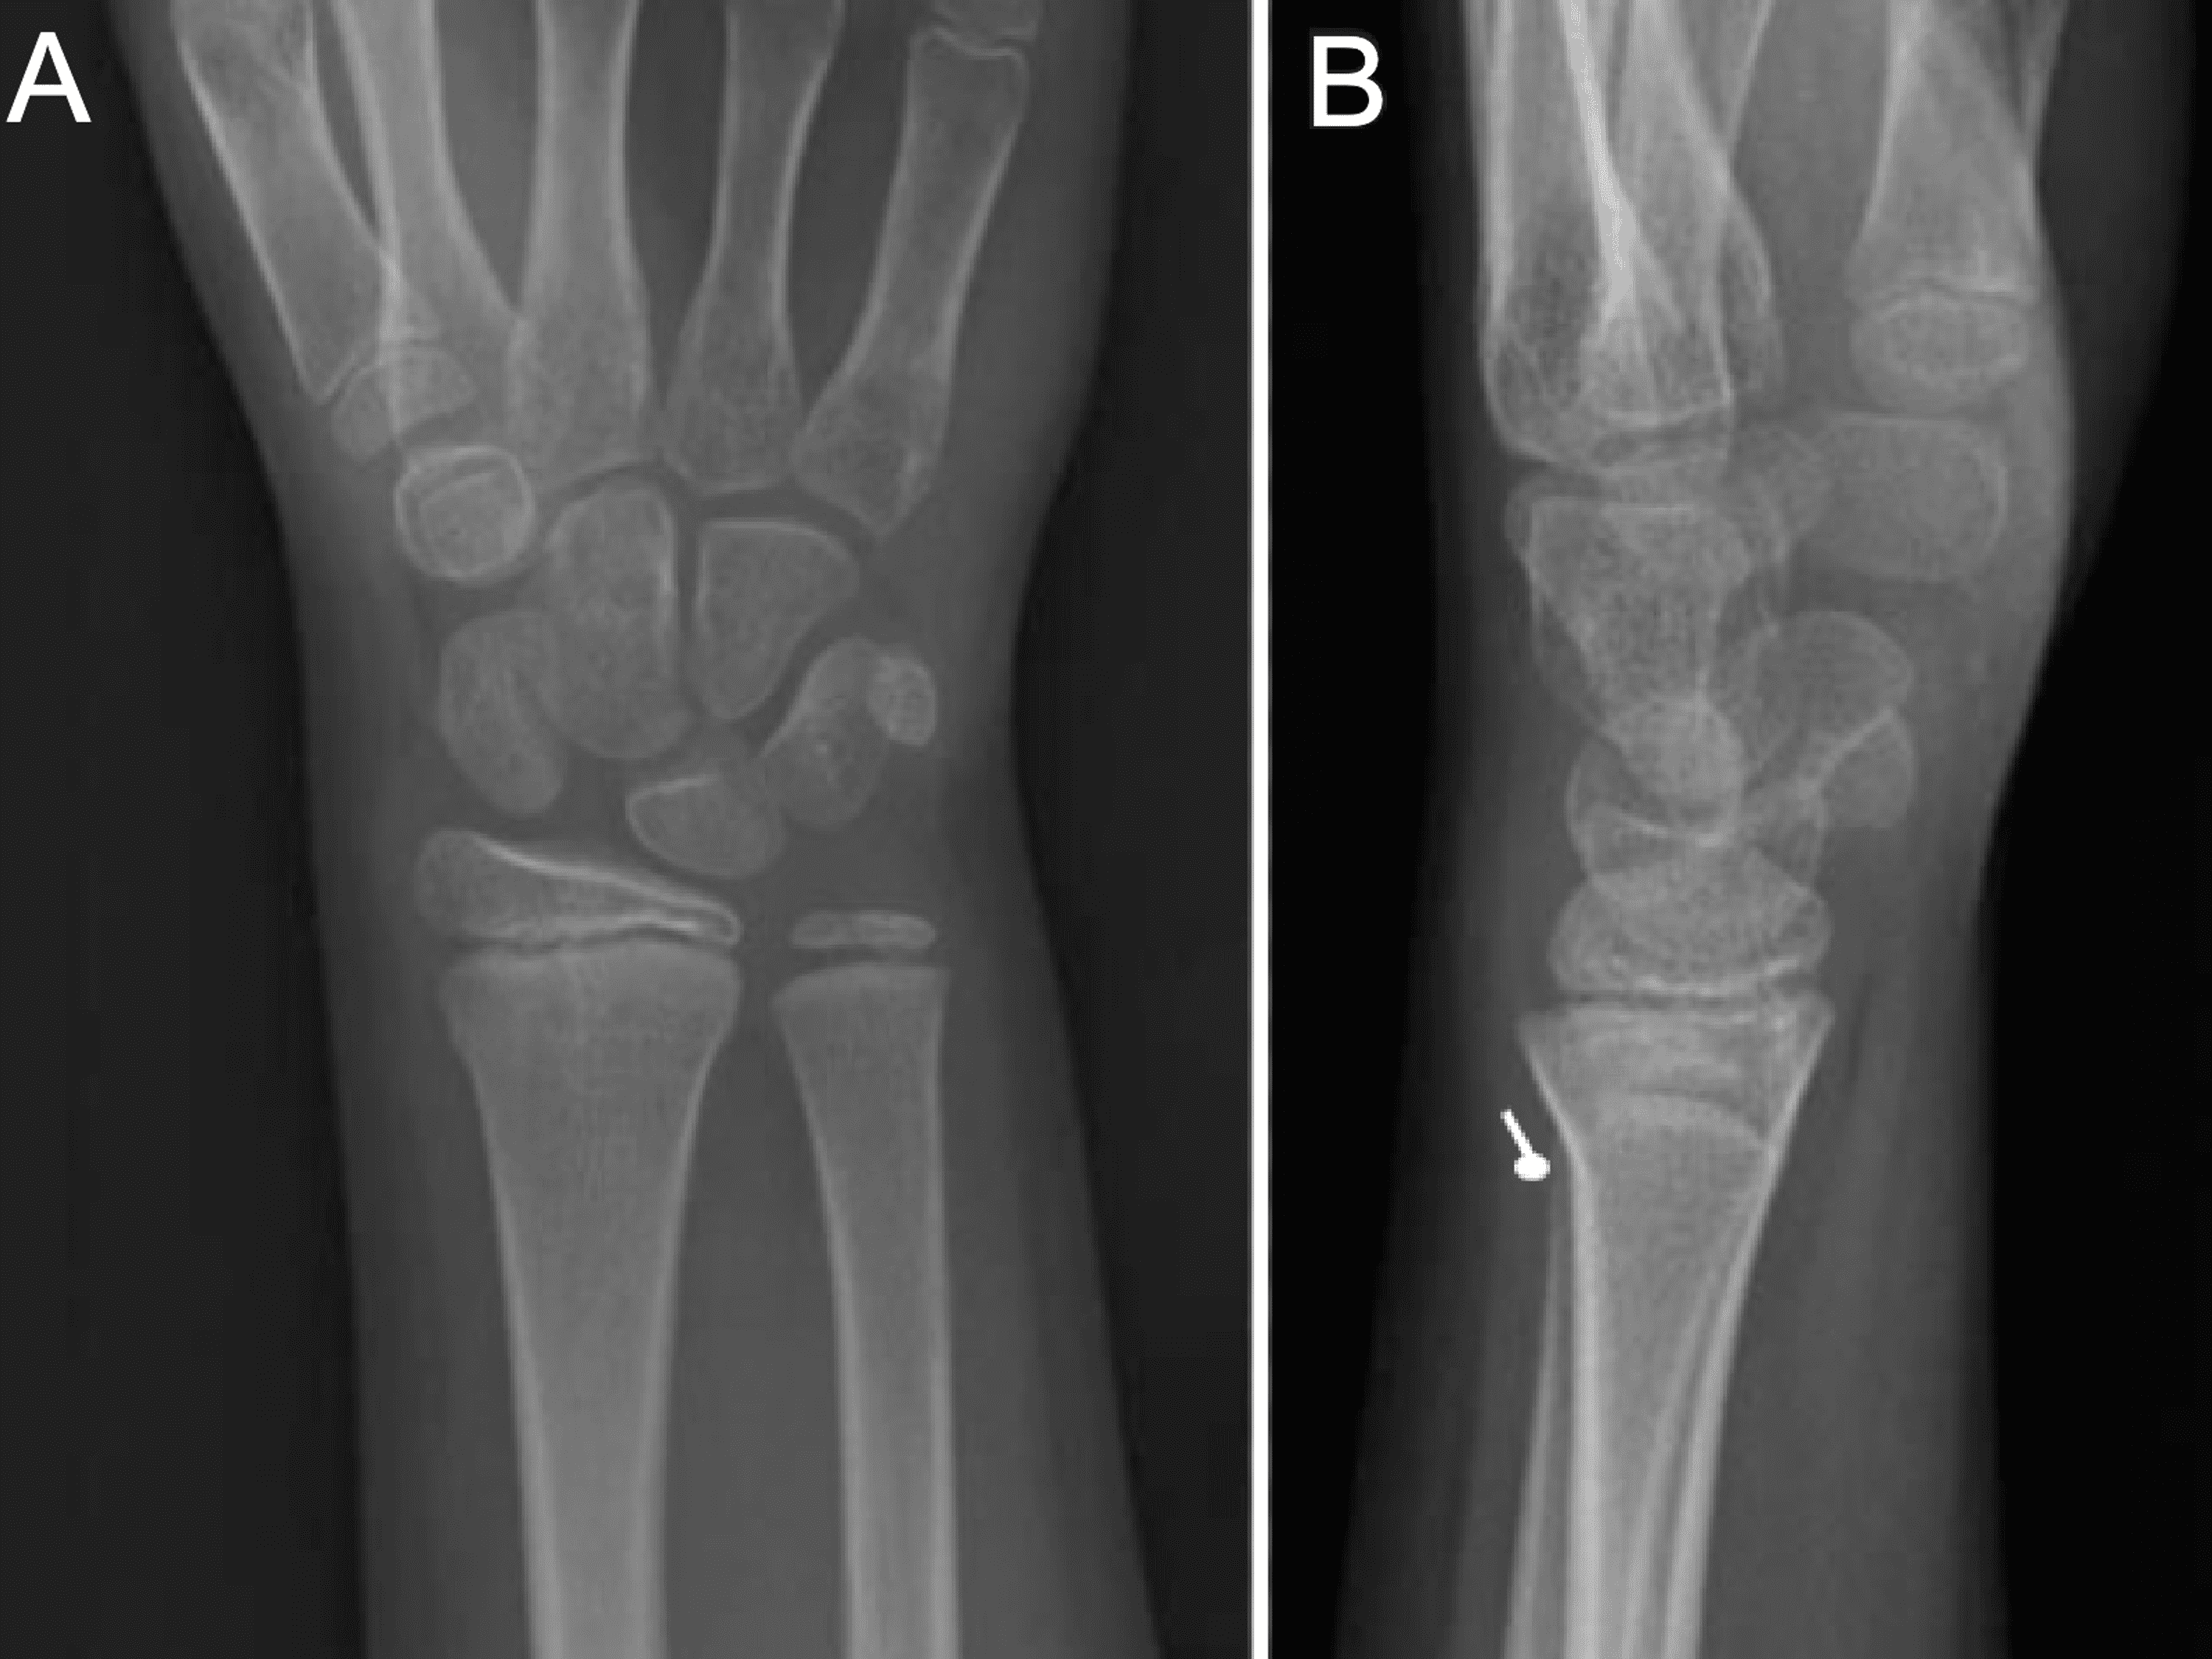

a Buckle fracture of distal radius. Posteroanterior wrist radiograph What Is A Buckle Fracture Of The Distal Radius A buckle fracture is sometimes referred to as an “incomplete fracture,” because the break is only on one side of the long bone of. A buckle fracture is an incomplete fracture where one side of the bone buckles or bends on itself; Distal radius fractures are very common. A fracture of the distal radius occurs when the radius — one. What Is A Buckle Fracture Of The Distal Radius.